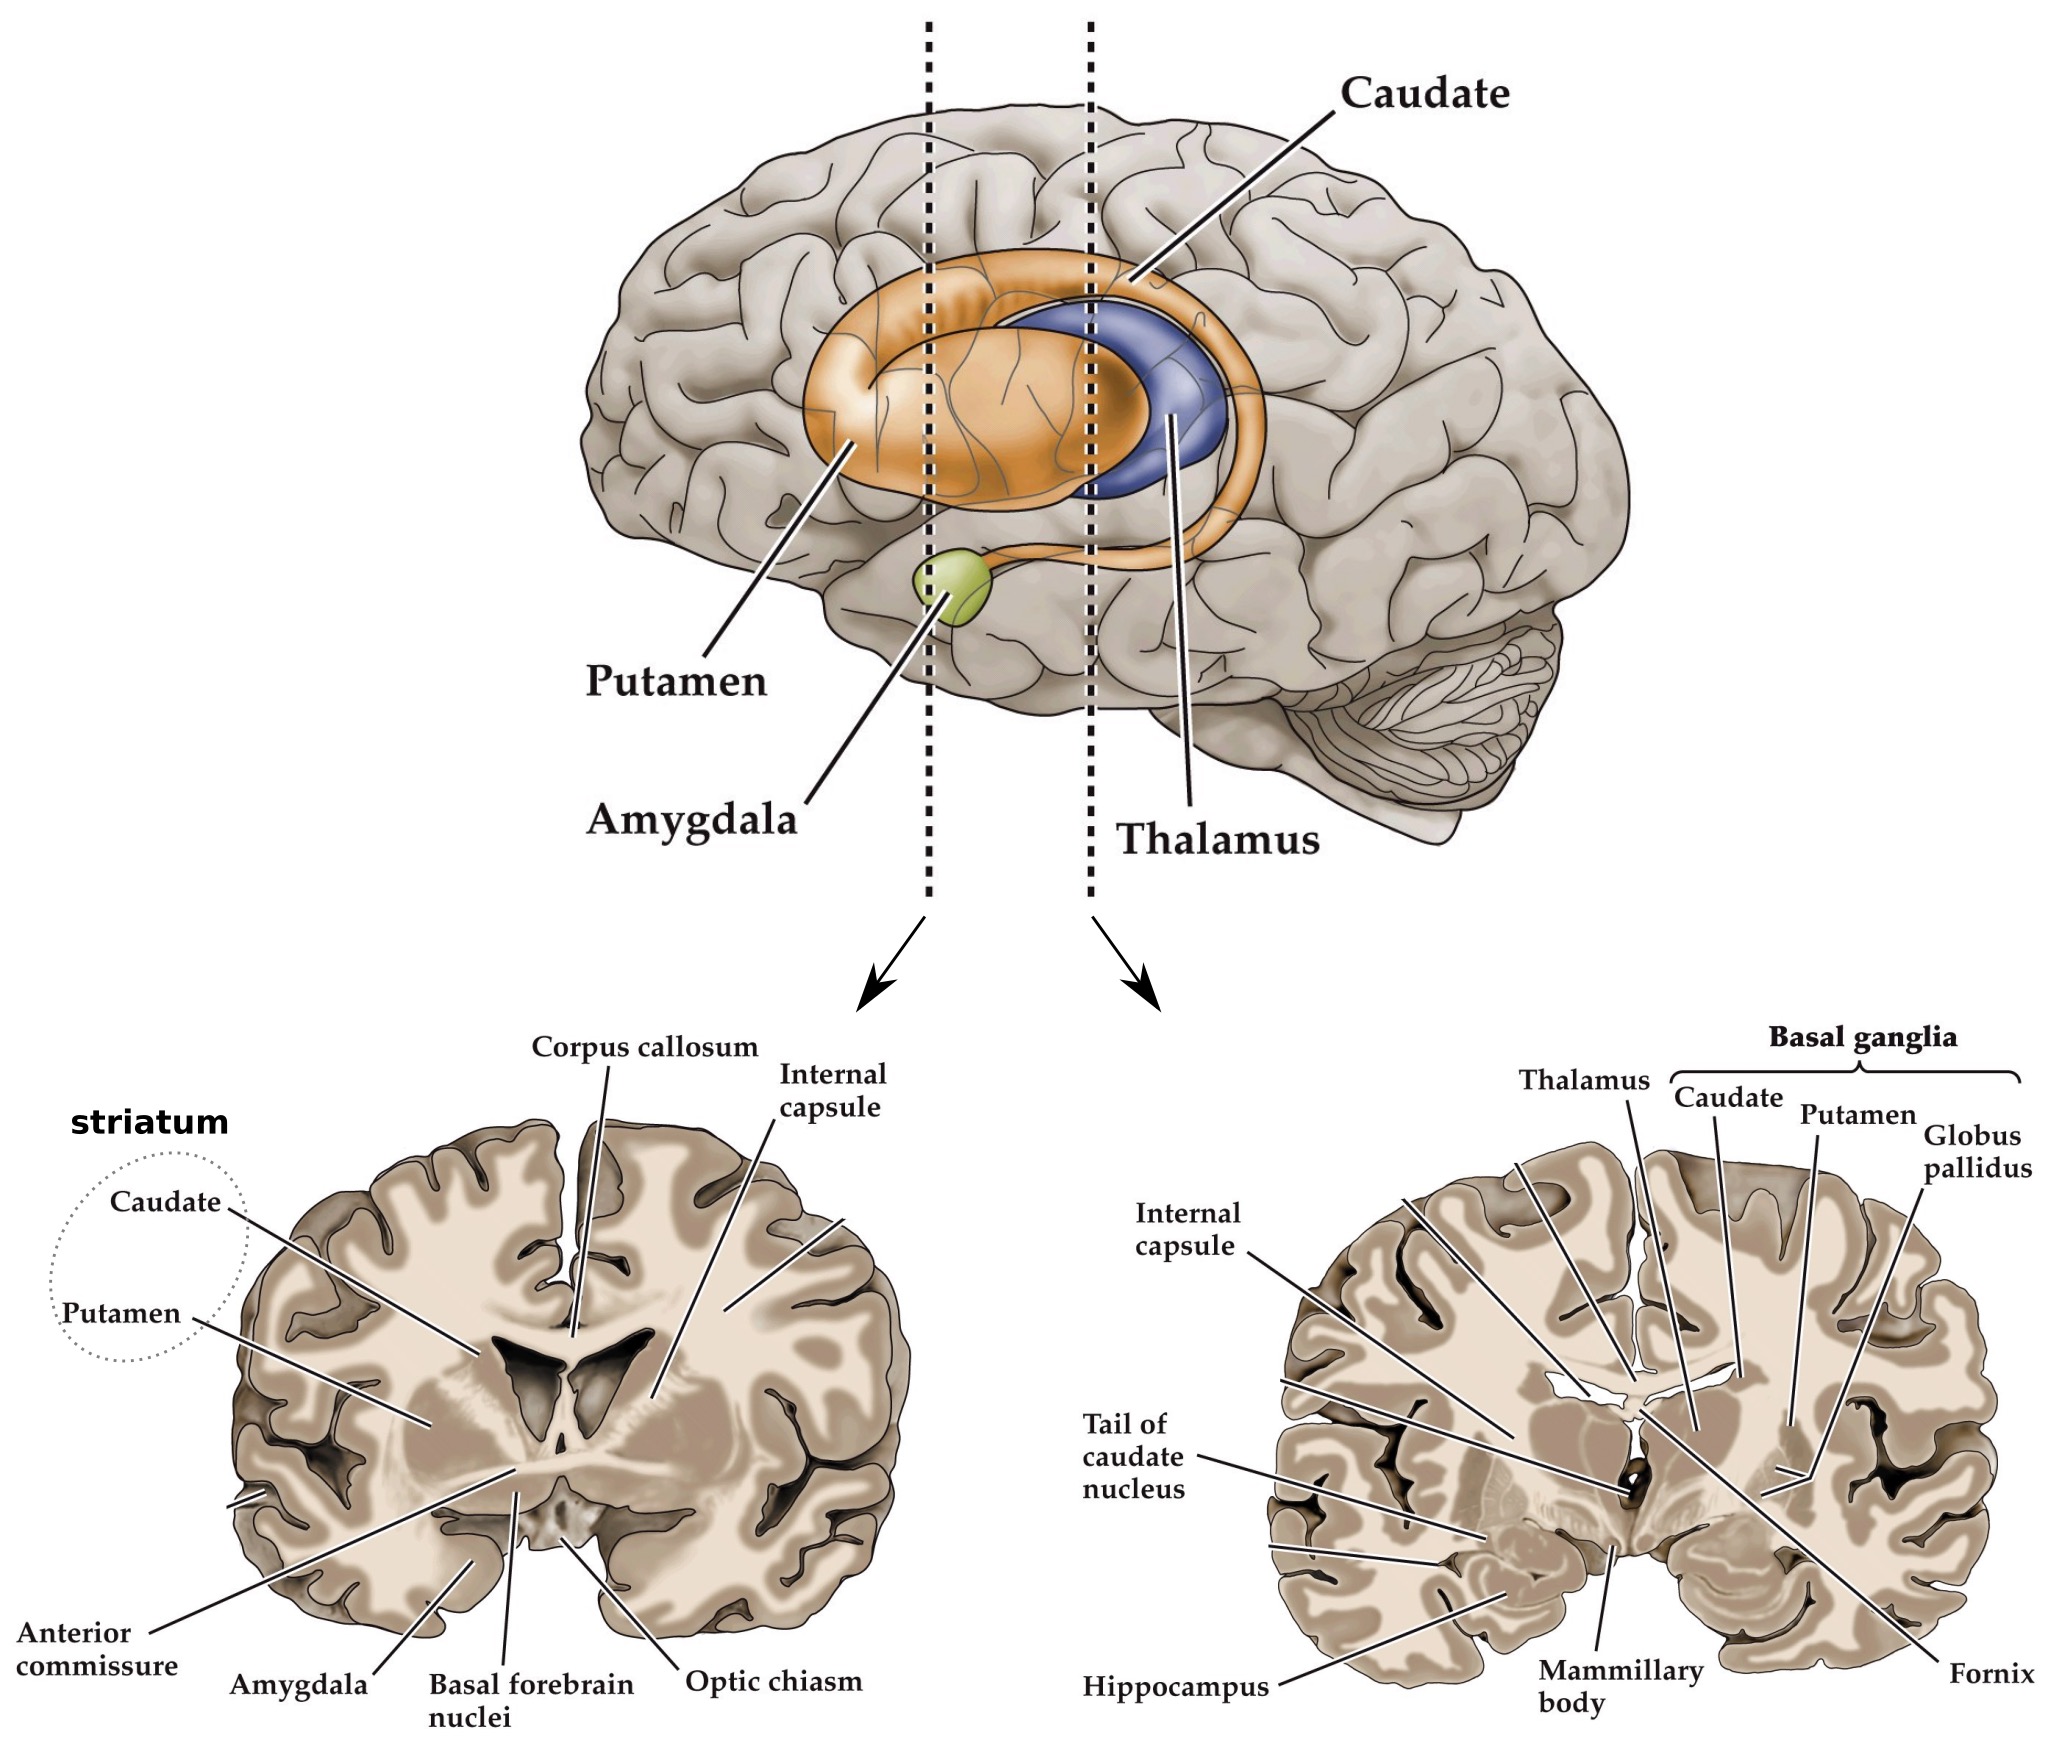

- Basal ganglia are a large set of nuclei that lie deep within the cerebral hemispheres

- Consists of striatum (caudate, putamen) and the globus pallidus

Corpus striatum

- Corpus striatum ('striped body') contains two portions– the caudate and putamen

- Function as the input zones for the basal ganglia

- Most regions of the cortex project to the striatum. Prominent innervation from the associational cortical areas of the frontal and parietal lobes. Collectively called the corticostriatal pathway

- Neurons in striatum that receive corticostriatal input are called medium spiny neurons. Large dendritic trees, integrate information from a variety of structures

Caudate and putamen separated by white matter (internal capsule) in mid to caudal coronal view sections of the brain

Anatomical location of the basal ganglia

Anatomy of the basal ganglia: caudate and putamen

Note:

Main input structures of basal ganglia system: Striatum– caudate and putamen

Main output structures of basal ganglia system: Globus pallidus interna (projects to thalamus) and substantia nigra pars reticulata (projects to superior colliculus; eye movements)

Intermediate nuclei in the basal ganglia system: Globus pallidus externa, STN, and substantia nigra pars compacta